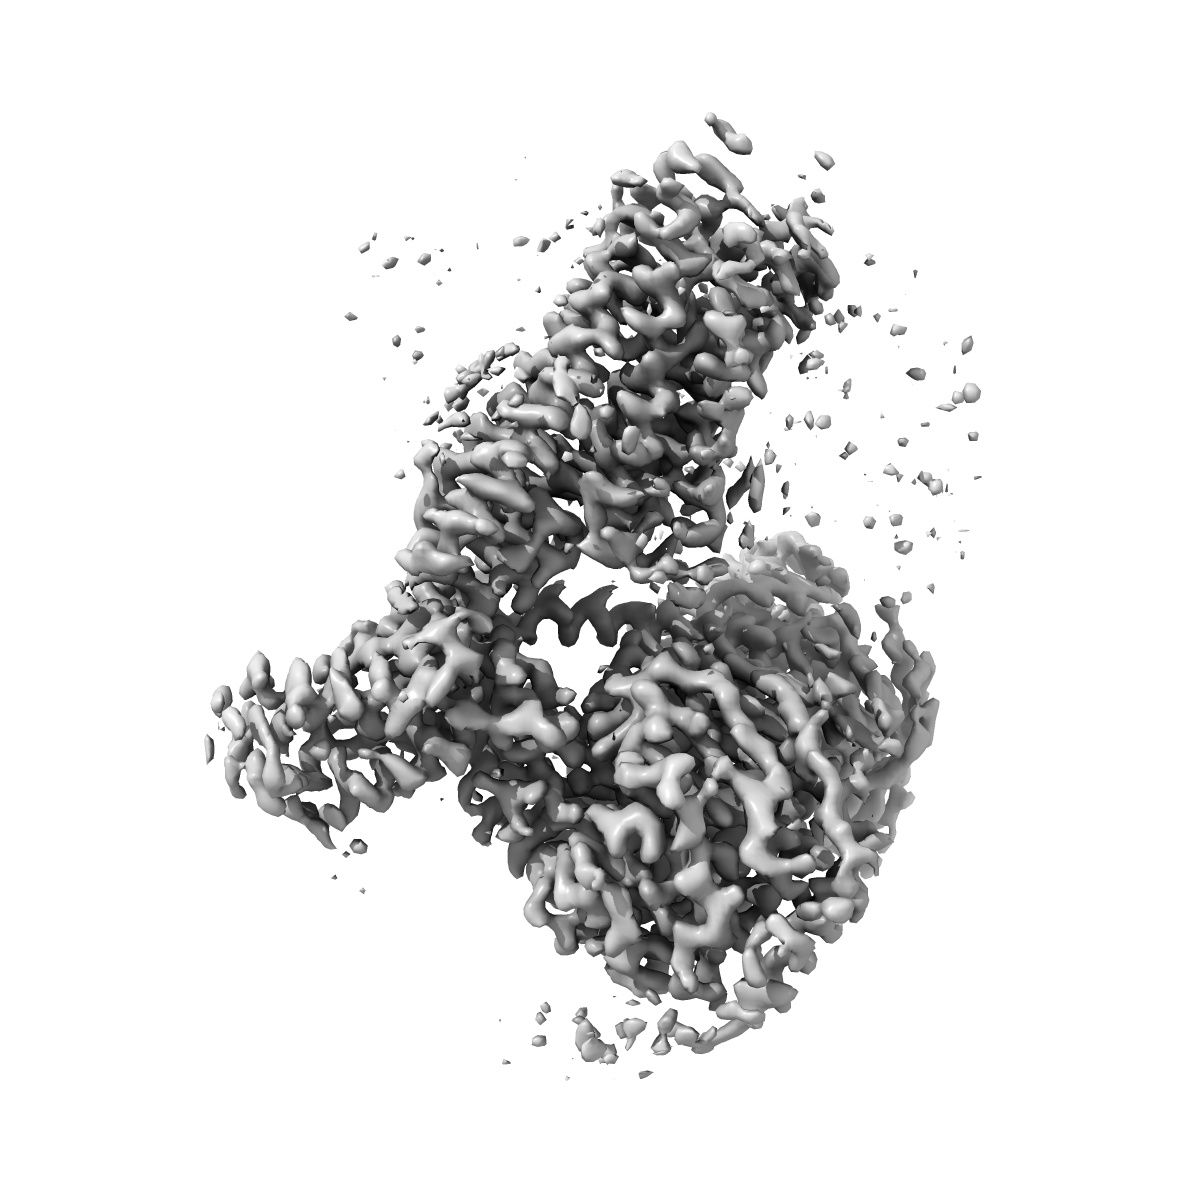

Gi bound nociceptin receptor in complex with nociceptin peptide

Single-particle3.28 Å

Sample: Gi bound mu-opioid receptor in complex with beta-endorphin

Structures of the entire human opioid receptor family.